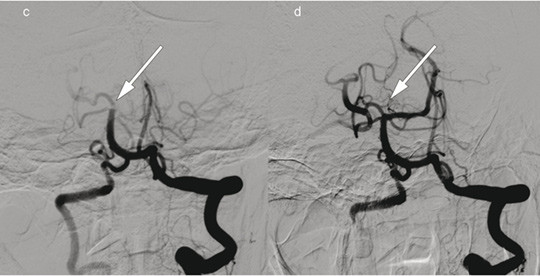

Pasient 2. En kvinne i 70-årene fikk etter hjertekirurgi akutt oppståtte høyresidige lammelser, svimmelhet og dysartri. NIHSS-skåren var 23 poeng (alvorlig hjerneinfarkt). Intravenøs trombolytisk behandling var kontraindisert. Bildet til høyre viser cerebral angiografi med kontrastinjeksjon i venstre a. vertebralis, c) før og d) etter embolektomi av stor trombe (piler) med okklusjon av a. cerebelli superior, a. cerebri posterior og basilaristoppen. Embolektomi ble utført med rekanalisering 220 minutter etter ictus. Hendelsen oppsto antakelig etter hjertekirurgien. Utredning påviste også atrieflimmer. Pasienten fikk antikoagulasjonsbehandling med warfarin, og ved kontroll etter tre måneder var NIHSS-skåren 0 poeng.

Mekanisk embolektomi på store intracerebrale kar kan være aktuelt både etter intravenøs trombolytisk behandling og i enkelte tilfeller der dette er kontraindisert (1). Endovaskulær revskularisering i fremre (pasient 1) og bakre kretsløp (pasient 2) kan føre til rask klinisk bedring.